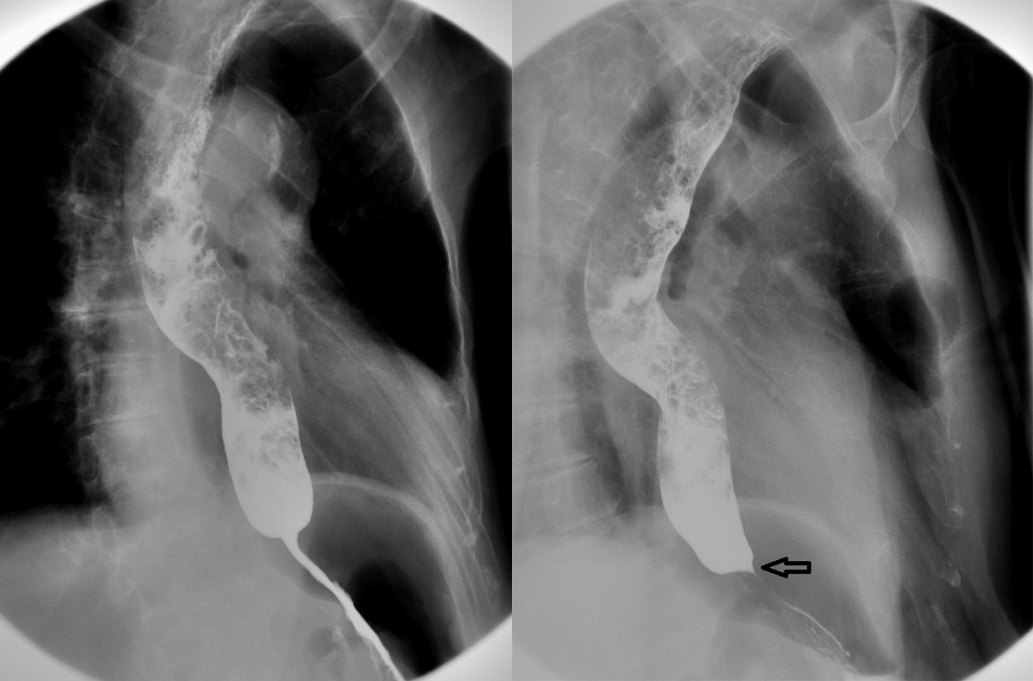

简要病史:女,63 岁,恶心、呕吐半天入院检查。既往有脑梗死、胆囊结石等病史。

胸部正位片示:食管明显扩张,气体潴留;双侧肺野弥漫性斑片状、网格状密度增高影。

食管钡餐造影示:食管全程扩张,大量气体潴留,食管下端管腔逐渐狭窄呈鸟嘴状,黏膜皱襞正常,钡剂通过受阻。

考虑为贲门失弛缓症。